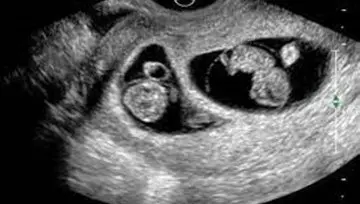

¿Qué se realiza en el ultrasonido de estos embarazos?

• ❤ Evaluación de la corionicidad, es decir si se trata de un embarazo gemelar con una placenta en la que ambos gemelos la comparten o bien dos placentas, una para cada gemelo, ya que de acuerdo a ello será la vigilancia en estos embarazos

• ❤ Si son embarazos gemelares con una sola placenta, la evaluación y el seguimiento deberá ser más estrecho, ya que que hay mayor riesgo de complicaciones en estos embarazos.

• ❤ La ecografía es el mejor método diagnóstico no sólo para identificar una gestación gemelar, sino también para catalogarla y especificar su corionicidad (número de placentas) y su amniocidad (número de bolsas).